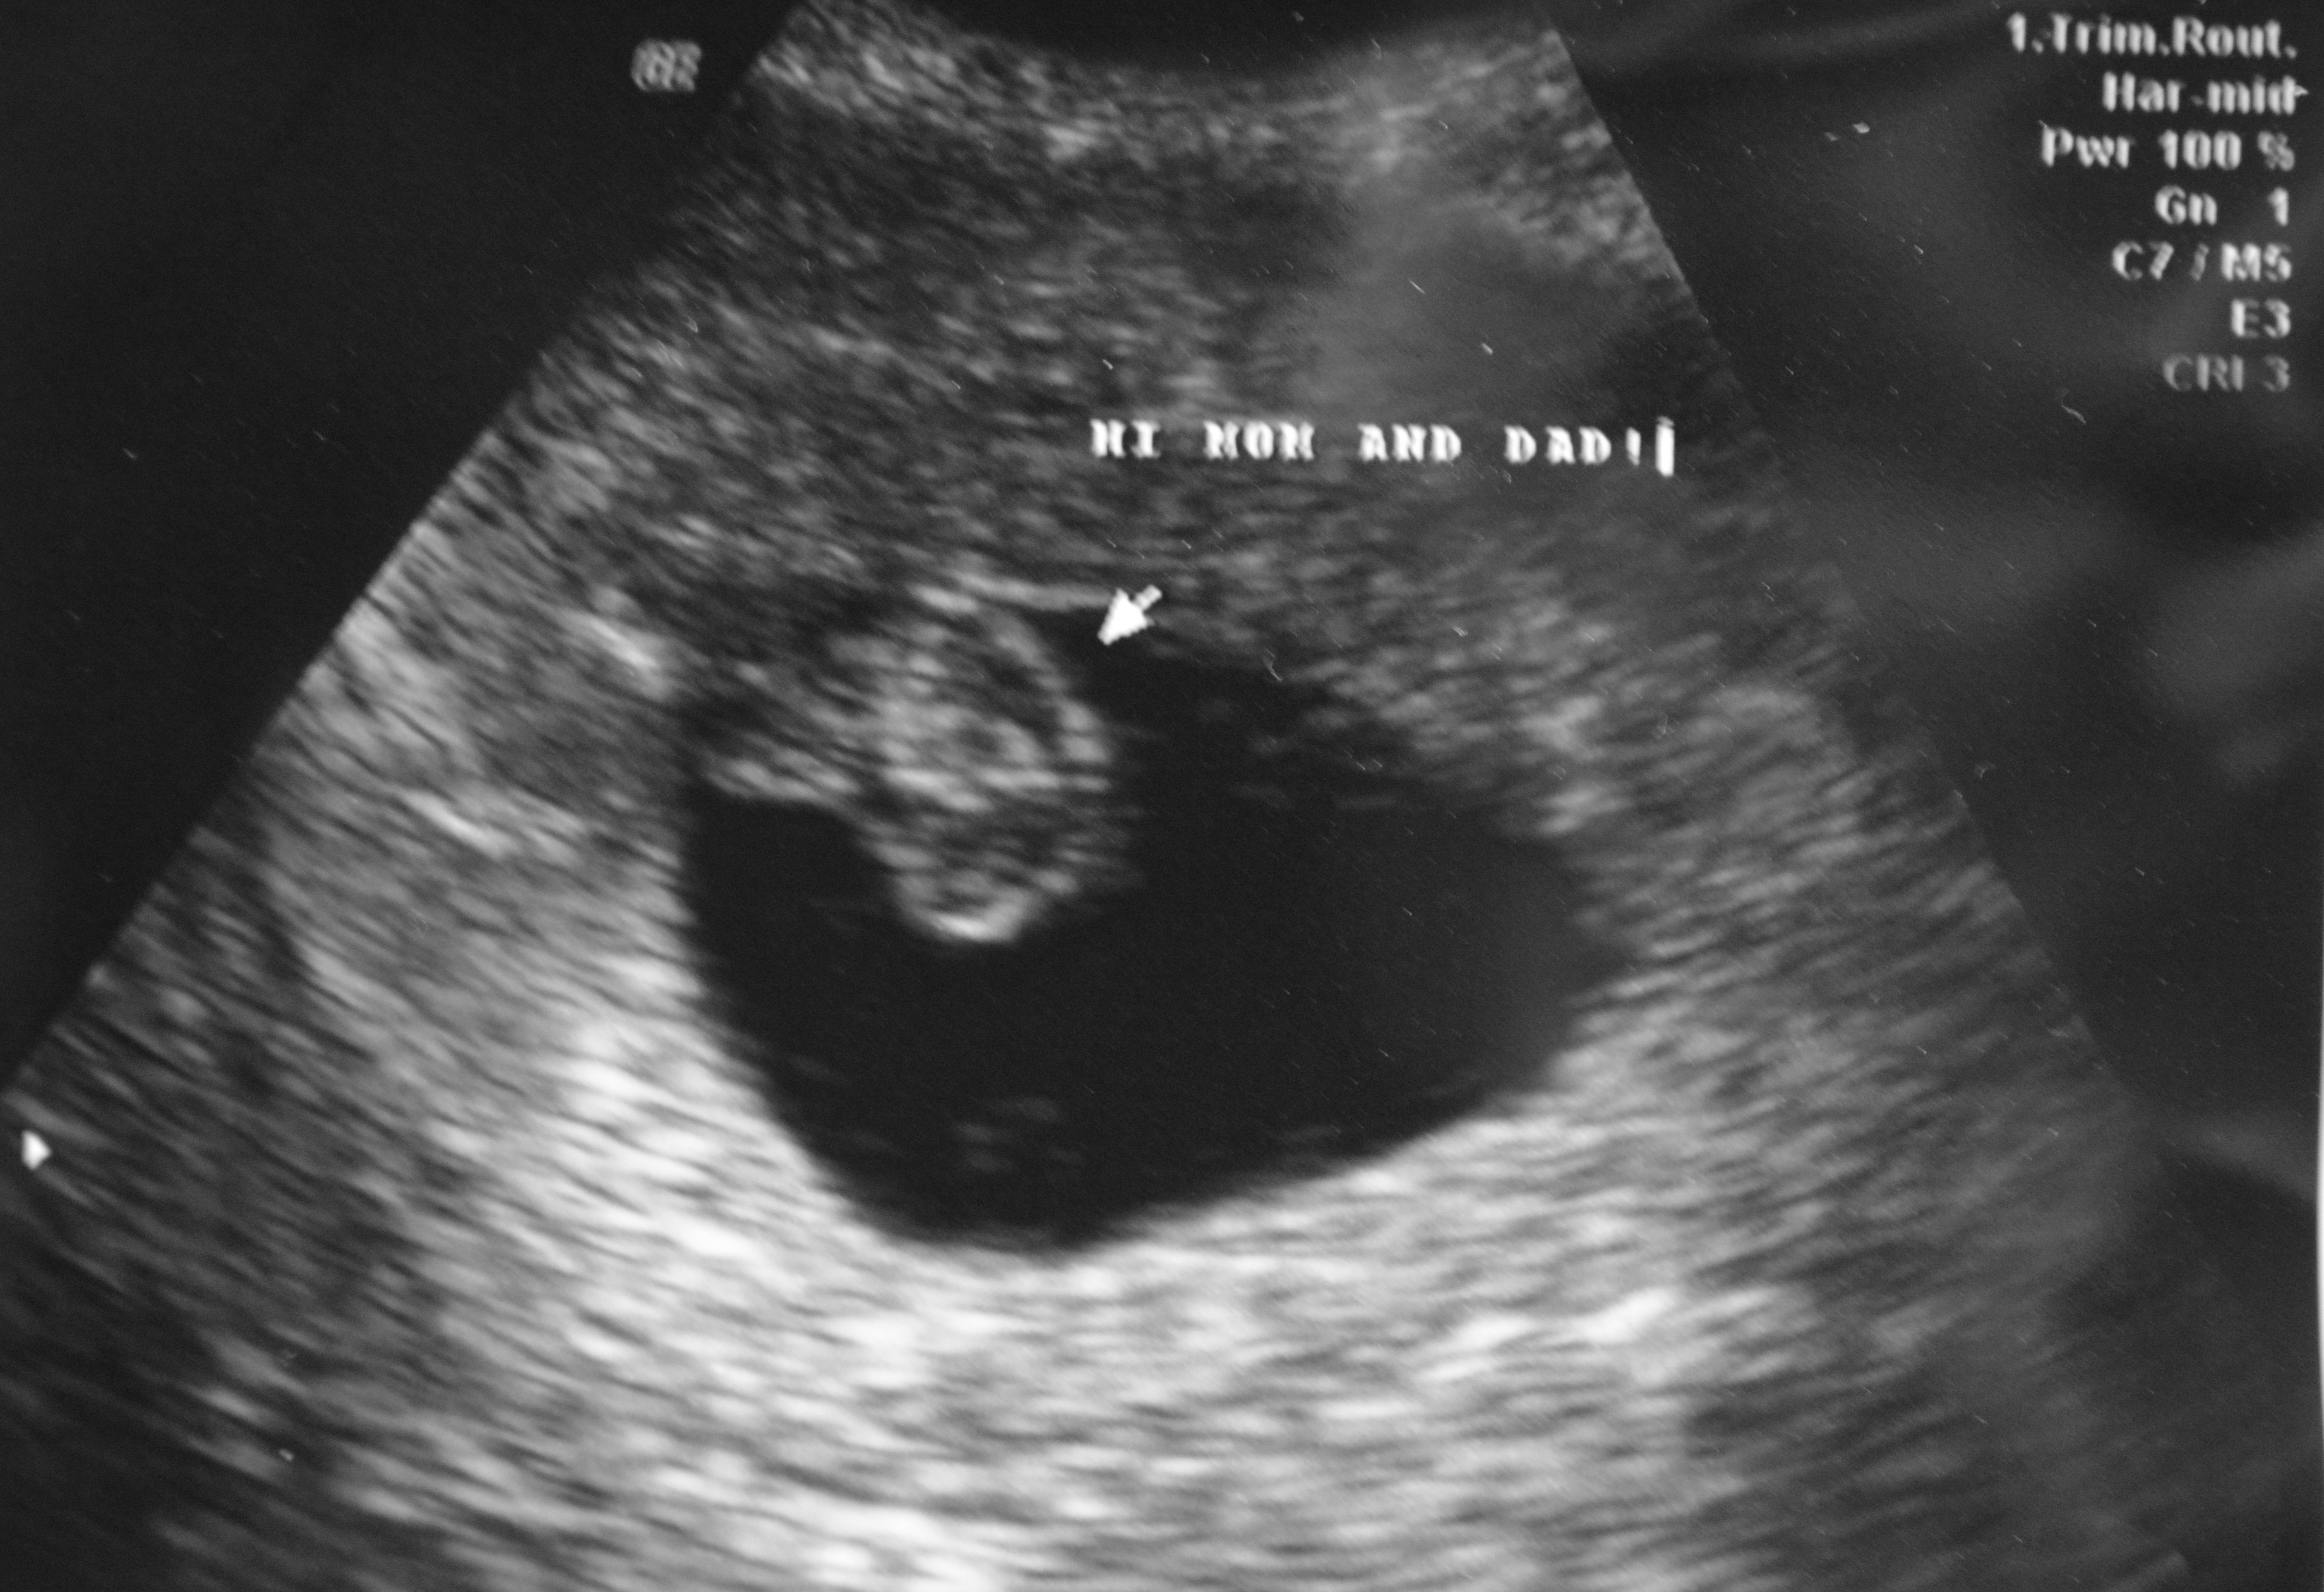

Our sweet little baby! DH says it looks like a goldfish We were so excited to see it! Heart beat was 138 bpm and they say everything looks great! The Dr. didn't even move the due date; which I was sure would happen! 7w5d